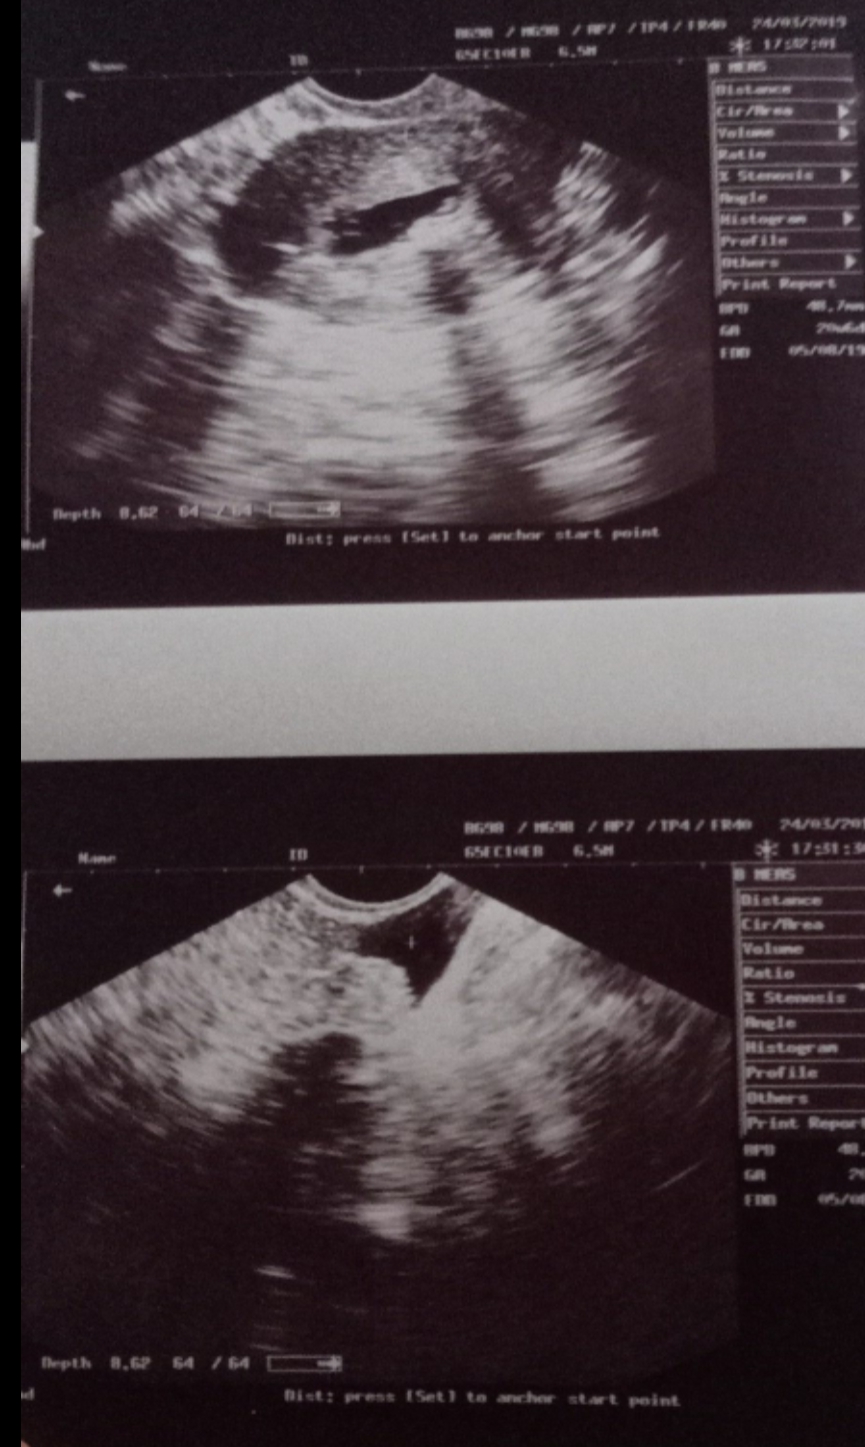

We actually trying to conceive but I have diagnosed with polyp at the fundus of uterus with the detail provide in suggest me to try COS+IUI for 2 cycle pregnancy not remained then will go for surgery...I have a question that , for my knowledge , the baby attaches itself to it so,then why Dr suggest me for COS+IUI?? IS pregnancy possible without removing polyp?? My weight is 66 ,my menstrual cycle regular,all hormonal test done n clear.

If the baby attaches over polyp then fetus can abort but if attaches to other surfaces anterior or posterior wall of uterus then the fetus will grow is possible without removing you tried medicine for pregnancy?For how many years are you married?

if all other normal,pregnancy possible without removing polyp but in case of prolong infertility or miscarriage polyp should be removed

I have all reports including semen analysis ,day 12 ultrasound,and all is normal but unable to achieve pregnancy it's been 4 yrs of being married